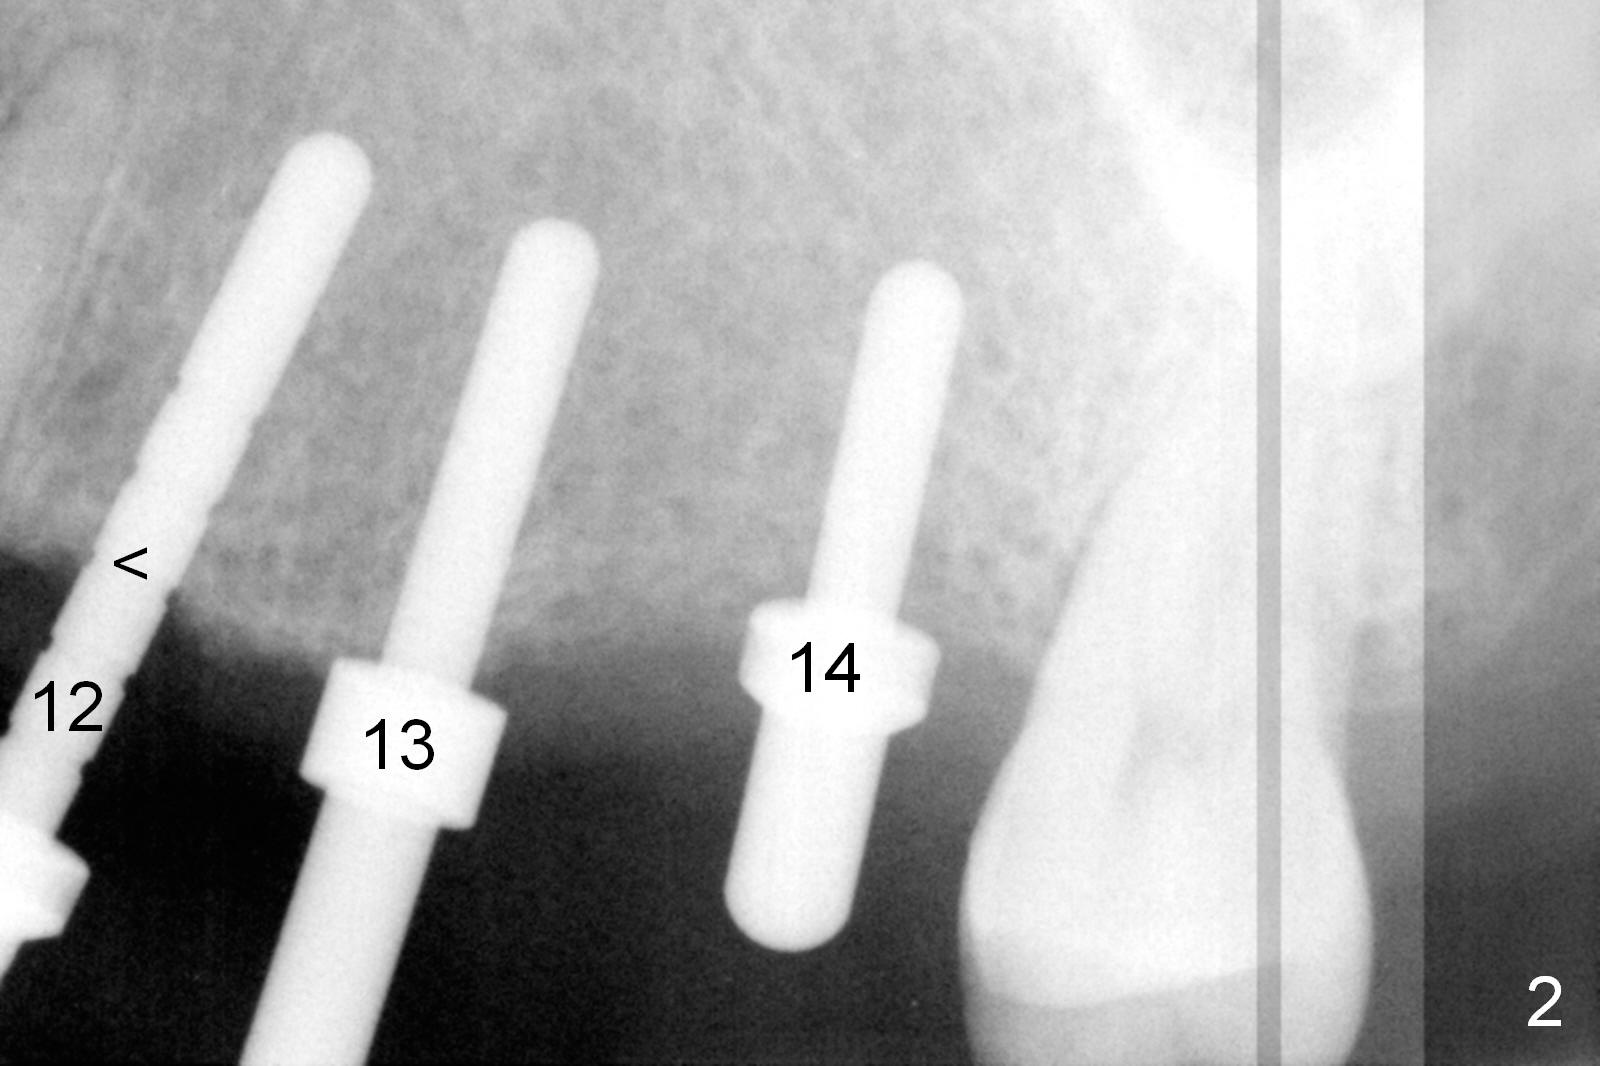

Initial osteotomies are established at the sites of #12-14 through the surgical guide (Fig.1). Following incision, the position of the osteotomies is adjusted buccopalatally where needed. Initial depth is 10 mm (Fig.2); final 14 mm. Ridge split is accomplished between the osteotomies with 7,10 and 13 mm saws from Esset Kit (Hiossen). The osteotomies are enlarged by bone expander drills from the Esset Kit RPM (Fig.3 D). When implants are placed (Fig.4 I (4.1, 3.8 and 5x14 mm)), the gap of split ridge does increase and is subsequently closed by bone graft and membrane. Definitive abutments (A) are installed to hold periodontal dressing in place securely. CBCT study reveals that the bone density between #12-14 are <200 Hounsfield units. When HU is >400, ridge split may result in bone fracture.